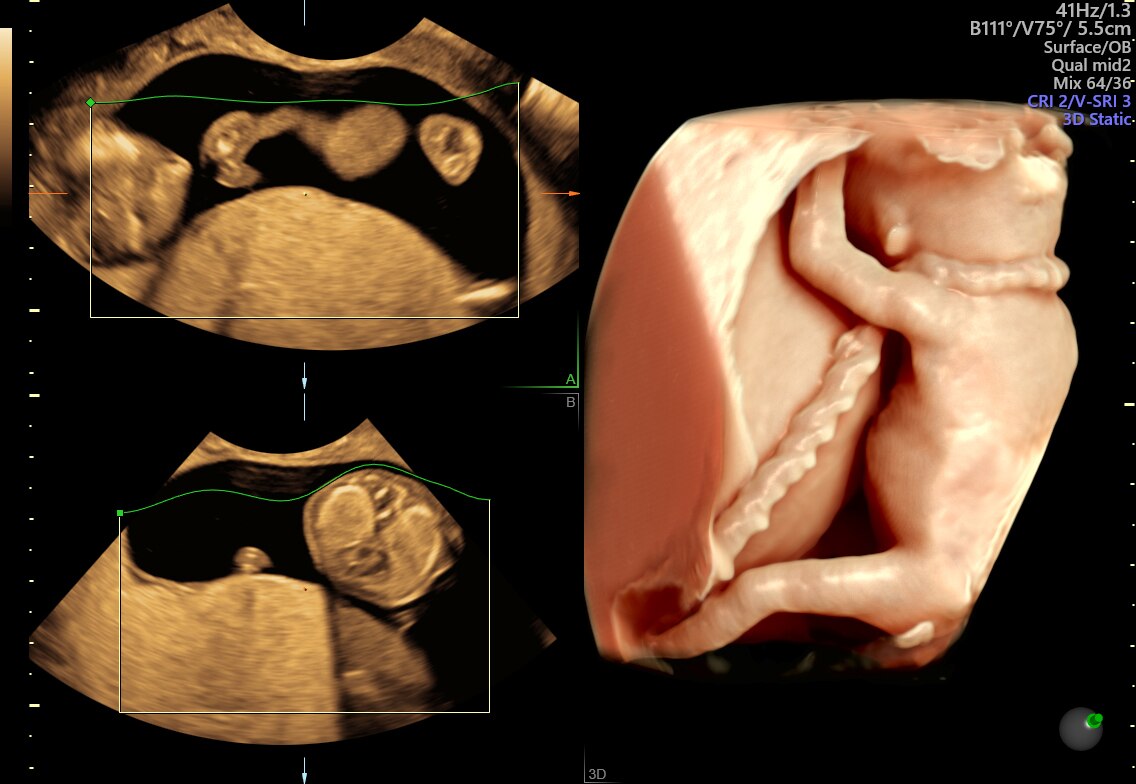

Fetus with HDlive™ generated with SonoRenderlive